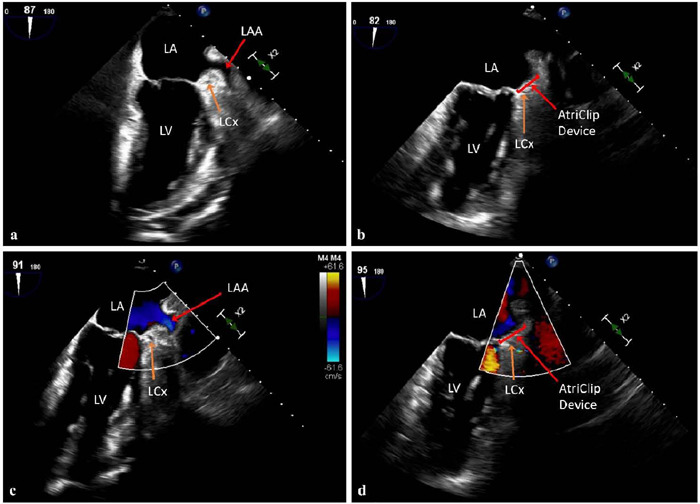

Off-pump robotic-assisted minimally invasive direct coronary artery bypass (MIDCAB) achieves revascularization without conventional sternotomy and provides benefit to patients that otherwise may not be ideal surgical candidates. For patients with comorbid atrial fibrillation, left atrial appendage exclusion may reduce stroke risk and is achievable via mini thoracotomy during concomitant MIDCAB. Here, we report four patients who underwent off-pump robotic-assisted MIDCAB and concurrent epicardial left atrial appendage exclusion. Intraoperative transesophageal echocardiography confirmed complete left atrial appendage exclusion in all cases. The concomitant robotic approach proved to be feasible, efficacious, and safe, with no postoperative mortality or stroke events during follow-up.